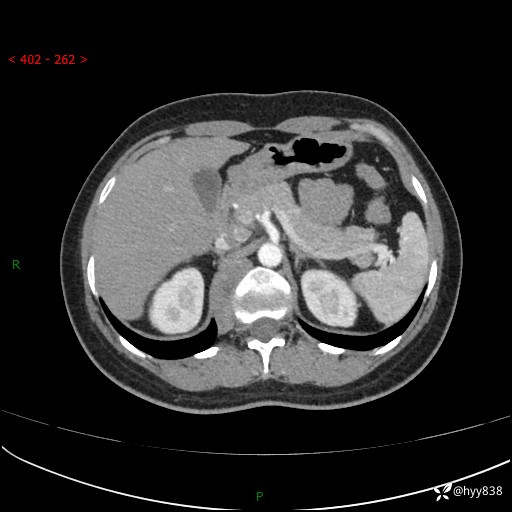

简要病史:患者于1天前因体检发现右旁肾占位,无肉眼血尿,无畏寒发热,无咳嗽咳痰,无腰腹部疼痛不适,无尿频尿急症状,起病来,患者未行特殊治疗,为求进一步诊治,门诊以"右侧腹膜后肿物"收治入院。 发病来患者精神、饮食、睡眠良好,小便如上,大便正常,体重无明显变化。

辅助检查:CT

临床诊断:腹膜后肿物

上腹部CT增强(动脉期+实质期)(外院平扫)